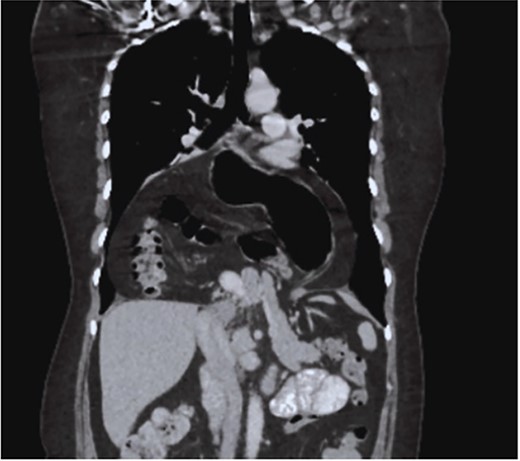

The case is reported of a 52-year-old woman, without significant illnesses, who presented with non-specific chest pain for 1 year, 6 months later with intermittent episodes of dyspnea with great and medium exertion, dysphagia, and heartburn. During the examination, hypoventilated lung fields at the bases, peristaltic sounds, and tympanism on percussion were heard. The thoracoabdominal tomography with contrast shows a diaphragmatic hernia containing the stomach, portions of the duodenum, pancreas, small intestine, and colon (Fig. 1), with a sac measuring up to 20 cm (Fig. 2).

CT coronal section, showing the presence of the stomach, duodenum, small intestine, colon, and pancreas.